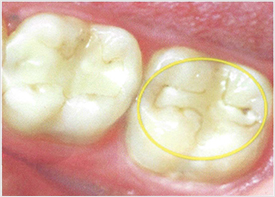

Fillings eventually fail A common misconception is that a filling will last forever. Composite resin fillings are durable, but they eventually will fail and need to be replaced. We consider a filling ....Dr. Rehder and the entire staff are friendly and compassionate. They accommodate my needs as a patient and treat me as a personal friend. Professionally, they provide the utmost care and advice, the patient always comes first. I can’t say enough positive comments about this practice.